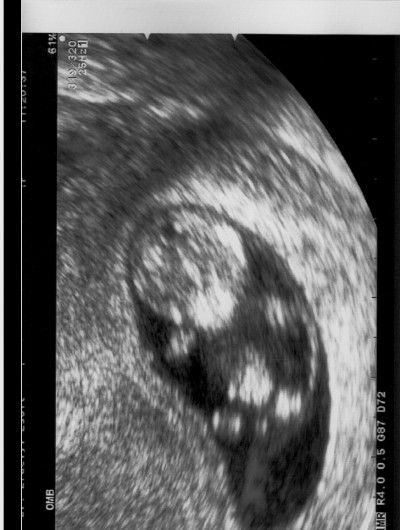

Szerdán megyünk az utolsó kötelező ultrahangra. Kíváncsi vagyok, hogy mekkora súlyt állapítanak meg Huninál.